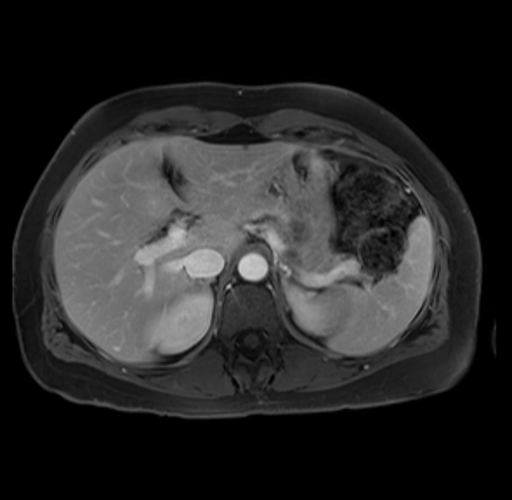

Laparoscopic distal pancreatectomy with possible splenectomy [case 14]

Imaging Analysis

Look through the patient's CT scan to identify any areas of concern for the necessary procedure.

Based on your CT findings, which issue(s) are present and would give reason for "planned slowing down moment(s)" in this case?

Considering a standard distal pancreatectomy procedure, what step(s) of the operation would you do differently in this case?